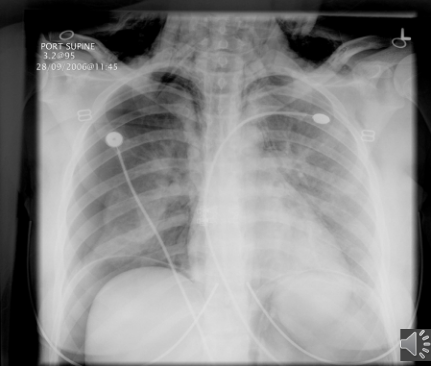

PT is 43 yr old male presenting with productive cough and fever/chills

What pathology is present?

pneumonia — alveolar/pneumococcal pattern